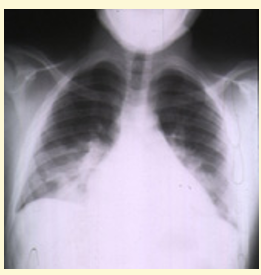

Life-threatening Complications - CHEST SYNDROME

1) Progressive hypoxia +/- fever

2) Pleuritic chest pain, patchy shadowing on CXR

Example of CHEST CRISIS in infant